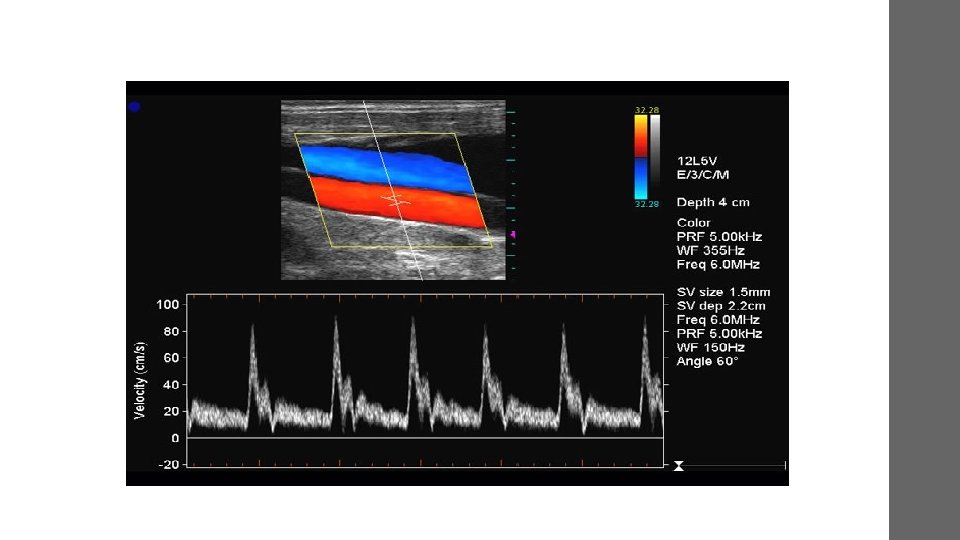

Doppler • Doppler ultrasound, a special application of ultrasound, measures the direction and speed of blood cells as they move through vessels. • The movement of blood cells causes a change in pitch of the reflected sound waves (called the Doppler effect). • A computer collects and processes the sounds and creates graphs or color pictures that represent the flow of blood through the blood vessels.

• the Doppler effect is used to measure blood flow velocity. • Ultrasound reflected from red blood cells will change in frequency according to the blood flow velocity. • When direction of blood flow is towards the transducer, the echoes from blood reflected back to the transducer will have a higher frequency than the one emitted from the transducer.

• When the direction is away from the transducer, the echoes will have a lower frequency than those emitted. • The difference in frequency between transmitted and received echoes is called the Doppler frequency shift, and this shift in frequency is proportional to the blood flow velocity.

• DOPPLER FREQUENCY SHIFT • The Doppler shift is the difference between the incident frequency and reflected frequency. • When the reflector is moving directly away from or toward the source of sound, the Doppler frequency shift (fd) is calculated as where f. I is the frequency of the sound incident on the reflector and fr is the frequency of the reflected sound. • Thus, the Doppler shift is proportional to the velocity of the blood cells.